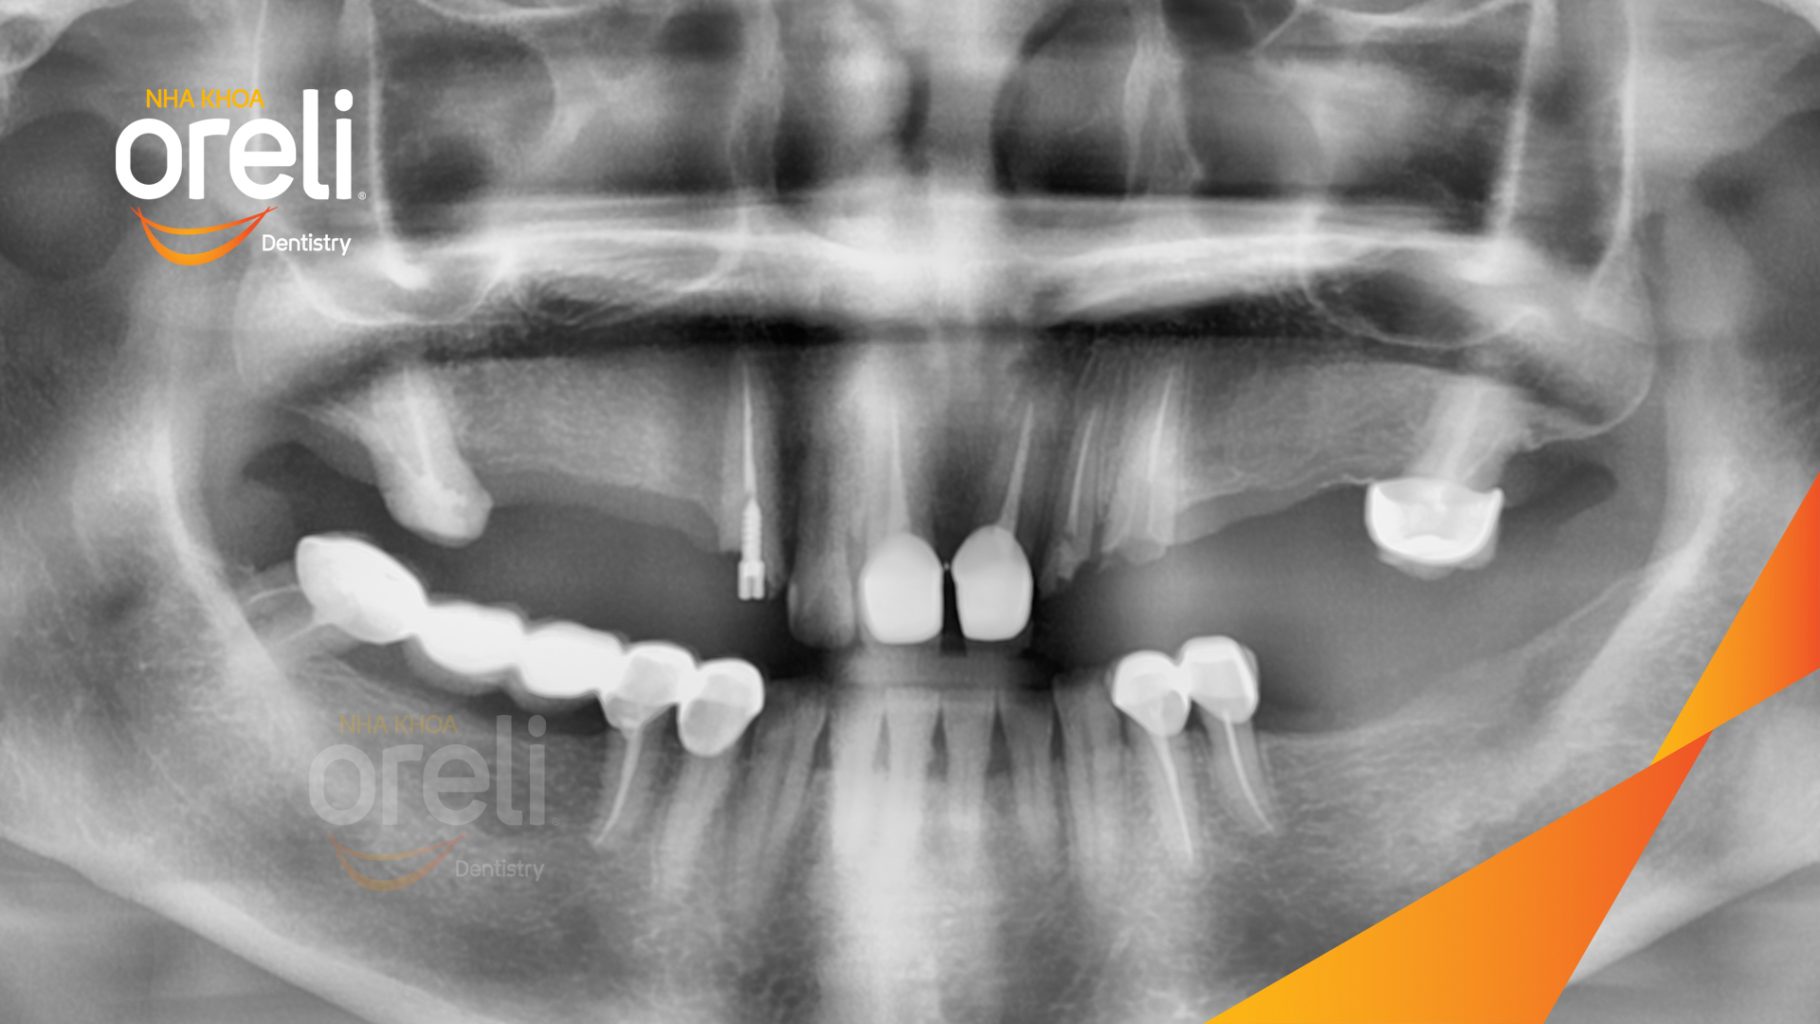

Tình trạng: Cầu răng sứ hàm trên lâu ngày gãy, viêm nướu, chân răng lung lay

Giải pháp: Cắt cầu răng sứ, nhổ răng, trồng răng implant

Hình ảnh thực tế